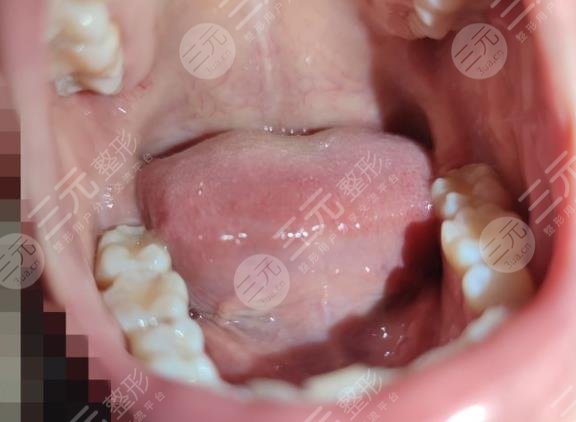

三、补完牙之后如何进行口腔护理

补完牙之后只是起到控制发展缓解症状的作用,因为牙齿本身并不能再生,所以在日常的生活当中要注意口腔环境的护理。在每日进食之后,建议早晚进行刷牙,平时进行漱口处理,清洁口腔异物,避免杂质的残留。另外每年都要到正规的医院进行洗牙治疗,可以有的减少牙结石,保持口腔环境的健康。另外要少吃一些含糖量比较高的食物,以免对牙齿造成腐蚀。不要吃过于坚硬的食物,以免牙齿出现破裂。如果口腔出现问题,一定要到正规的医院进行治疗,及早的控制疾病的进展。